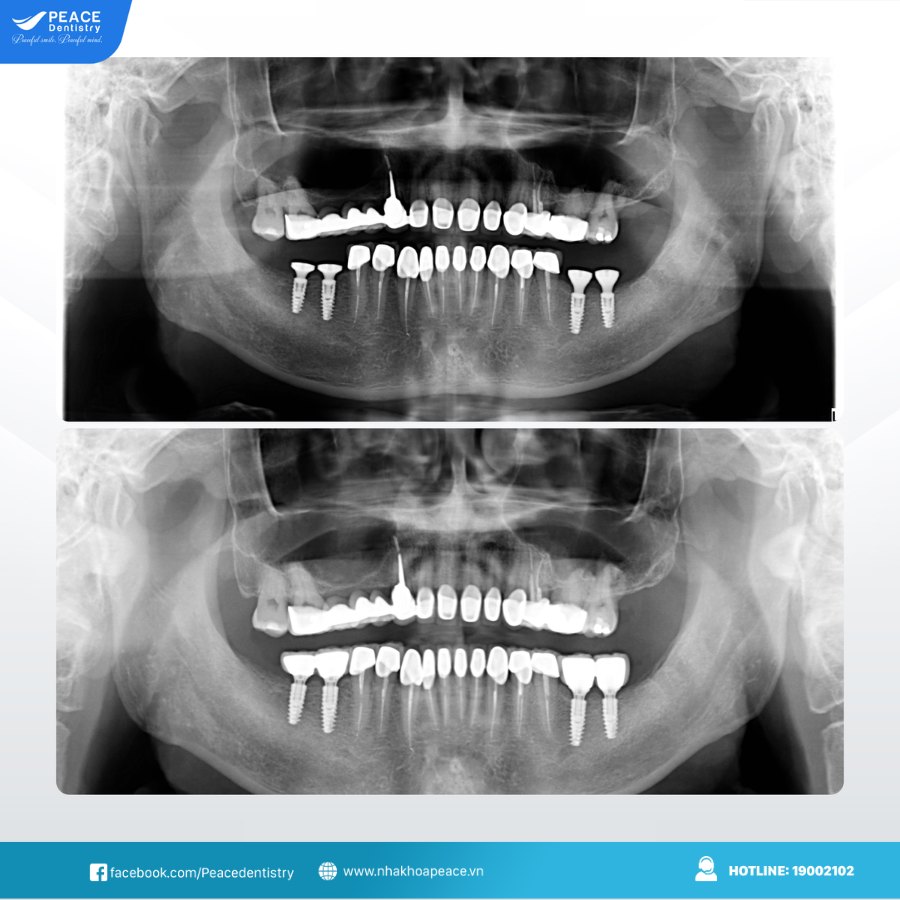

(Hình ảnh khách hàng tái khám implant sau 10 năm tại Peace Dentistry)(**)

(Ca trồng răng implant có thể bị thất bại nếu không được thăm khám, kiểm tra theo đúng chỉ định của bác sĩ)(**)